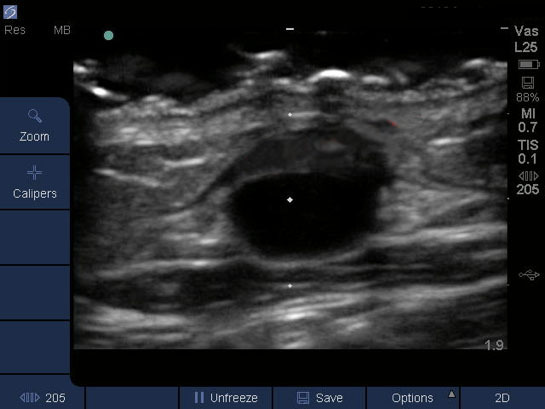

Dialysis Anterior Wall Injury Image